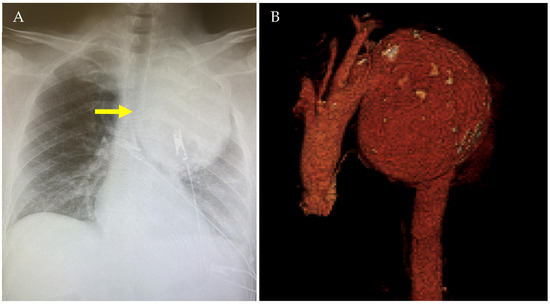

| Current Case-1 | 48 | M | Aortic arch | Cough | 25 years | Hybrid (ET + TEVAR) |

| Current Case-2 | 46 | M | Aortic arch | Asymptomatic | 21 years | Hybrid (carotid-subclavian bypass + TEVAR) |